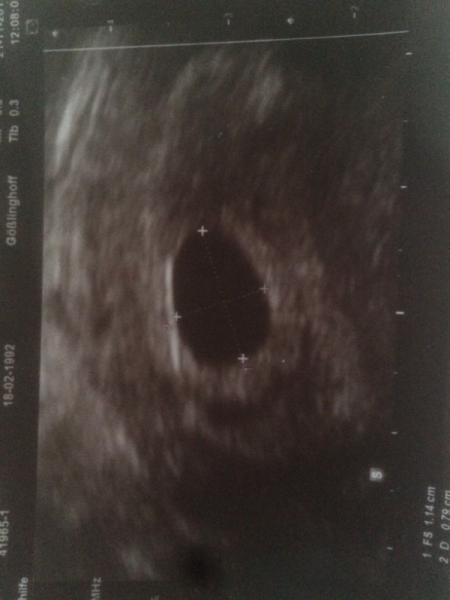

Hallo ihr lieben Ich bin total verzweifelt! Mein Freund und ich sind seid fünf Jahren zusammen und seit drei Jahren wollen wir ein Baby. Verhütet haben wir allerdings schön länger nicht mehr und die Pille hab ich das letzte mal mit 17 genommen bin jetzt 25 . Vor zwei Wochen dann die große Freude endlich schwanger . Doch vor zwei Tagen war der schöne Traum dann vorbei nach mehreren US und Blut Test diagnostiziert mein FA ein Windei. Ich bin sehr verzweifelt Der Arzt lässt mich nun entschieden ob ich eine AS machen lasse oder warte bis es von allein geht was allerdings dauern könnte,eine AS wäre bei mir nicht zwingend notwendig nur die schnellere Lösung. Ich habe mich eigentlich schon fürs warten entscheiden da ich Angst vor der op und den möglichen Folgen habe. Nun meine Frage Hat schon jemand Erfahrung mit einem Windeie gemacht und einem natürlichen Abgang und ist es danach schwieriger schwanger zu werden ? Gibt es etwas um den natürlichen Abgang zu fördern?

Bild zu Windei was nun? - Kinderwunsch - was tun, um schwanger zu werden?

Konnte man mir bis jetzt nicht sagen meine letzte Mens war am 20.9 da mein Zyklus sehr unregelmäßig ist kann man nicht wirklich bestimmen wann mein ES war . Die fruchthöle war aber beim letzten US komplett leer und der hcg wert nur minimal angestiegen es deutet also alles auf ein Windei hin